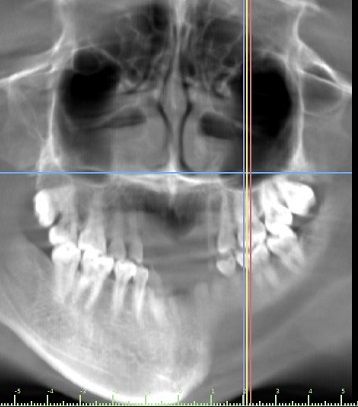

Trước đây, các bác sĩ lên phương án phẫu thuật dựa trên phim chụp từ máy Ct cone beam.

Hình ảnh trên phim có những chỗ khuất, mờ,... nên khi phẫu thuật không chính xác.